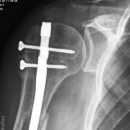

Dislozierte subcapitale Fraktur mit Tbc majus